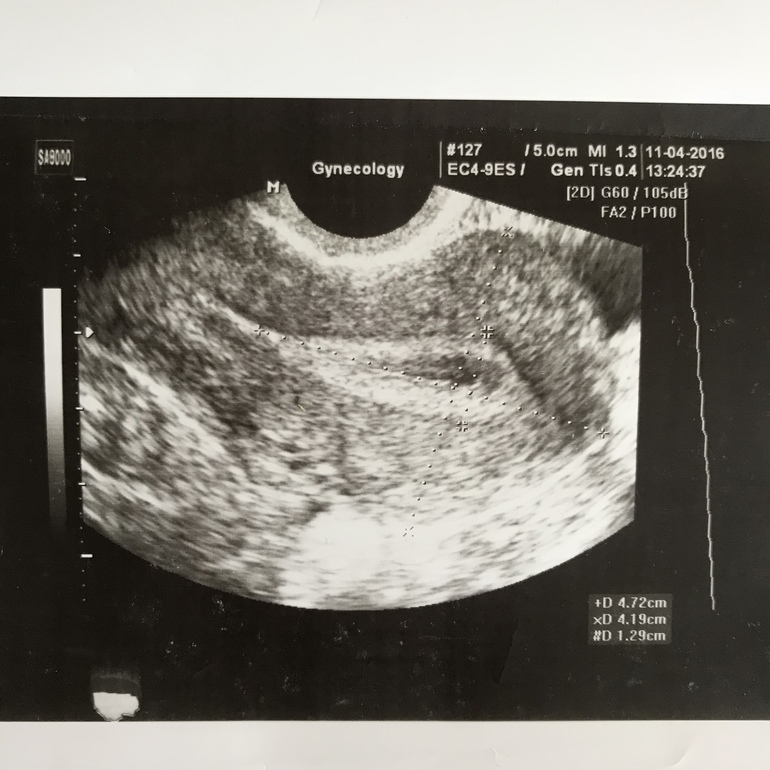

И вот для сравнения УЗИ матки небеременной просто в середине цикла. Точно такая же как при кисте и 2х полосках тогда

Я своими глазами видела, могу даже дома поискать, у меня на сроке 5 недель есть УЗИ матки с двумя беременностями и то узи с кистой. Матка маленькая там и никакого намёка на беременность. А срок одинаковый на всех 3х узи